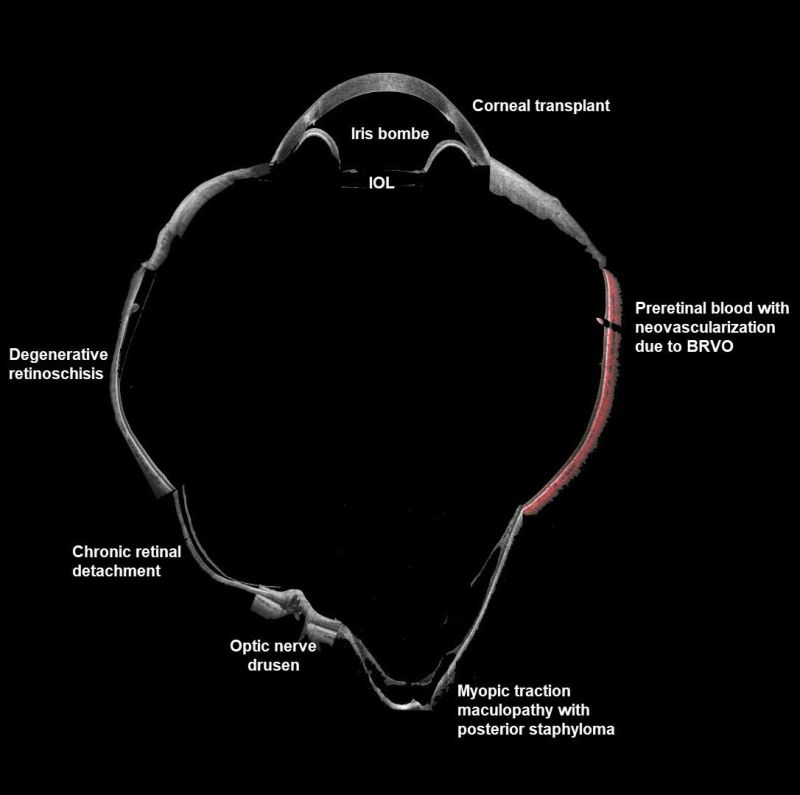

Малюнок 1. Очні патології на одному зображенні. Зображення надане доктором медицини Барбарою Пароліні, керівником вітреоретинального відділення Очної клініки, Брешія, Італія.